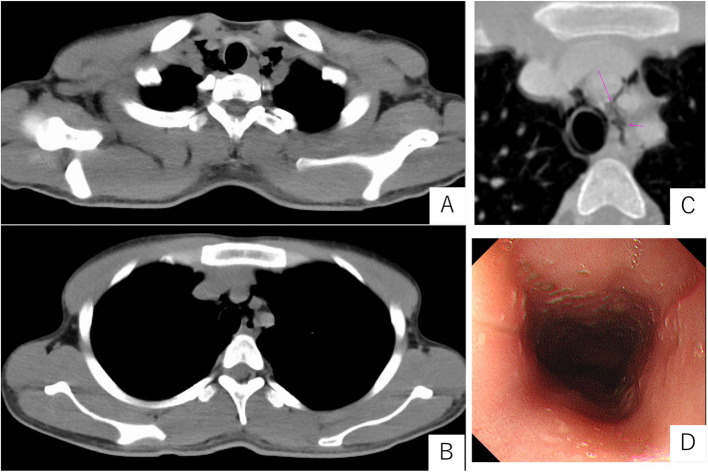

Case presentation: A 20-year-old foreign technical intern visited to a hospital because of nausea and shortness of breath. He had been diagnosed with diabetes in his home country and had initiated insulin therapy; however, since arriving in Japan, he had not accessed any medical services. Computed tomography revealed pneumomediastinum, while laboratory tests showed marked hyperglycemia, metabolic acidosis, and a significantly elevated blood ketone level (15,044 µmol/L). The patient was diagnosed with Hamman's syndrome associated with DKA. Upper gastrointestinal endoscopy showed no evidence of gastrointestinal perforation. Conservative intensive care, including insulin therapy and fluid resuscitation, resulted in clinical improvement.